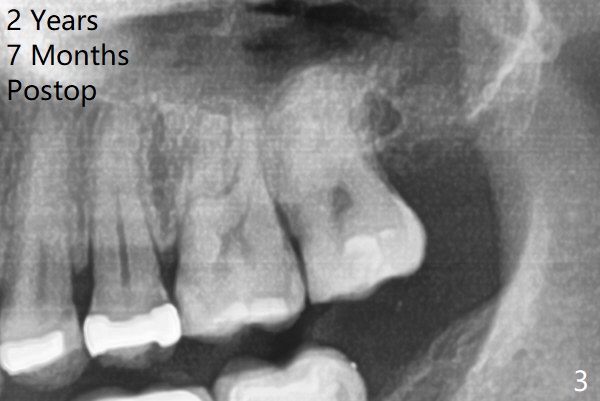

A 37-year-old man complains of food impaction between #14 and 15. Panoramic X-ray shows mesioangular impaction of #16 (Fig.1 ^), which may press #15 root to rotate the tooth so that there is a diastema between #14 and 15. When the impacted tooth is removed, it looks like a microdontia. Intraop X-ray reveals a normal sized 3rd molar in situ (Fig.2: 16). Therefore the microdontia removed is a supernumerary tooth. The tooth #16 is then extracted. The diastema appears to persist 2 years 7 months postop (Fig.3), although gingival swelling and pain reduces. The follow up panoramic X-ray reveals a significant increase in PARL at #20. Return to Professionals Xin Wei, DDS, PhD, MS 1st edition 05/14/2020, last revision 05/16/2020